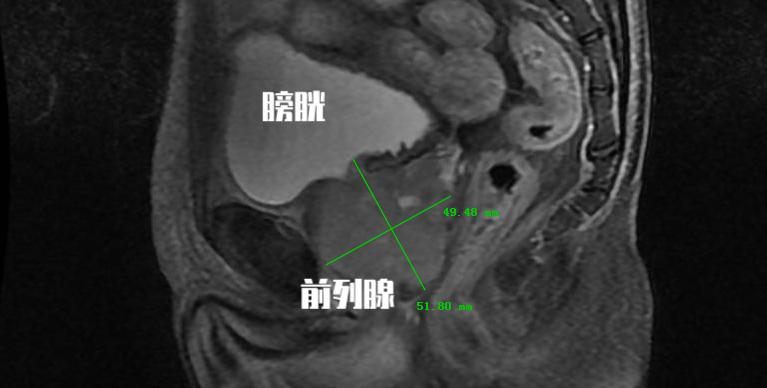

从PSA的分泌来源中我们不难看出,随着前列腺体积增大, 前列腺增生组织也会分泌PSA 。所以对于很多老年男性患者,虽然PSA水平增高,但是在核磁共振检查和前列腺穿刺活检中都最终证实并不是前列腺癌。

前列腺特异性抗原密度(PSAD)是测算血清总PSA值与前列腺体积的比值,正常值≤0.15。比值越高意味着越有可能为具有临床意义的前列腺癌。